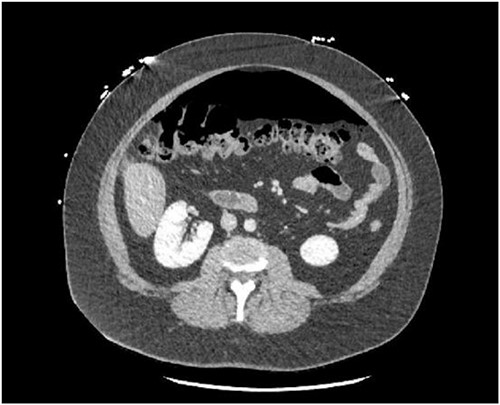

A 30-year-old female presented to the emergency department due to severe abdominal pain that had started suddenly 5 h prior to arrival. Symptoms began after eating dinner. She had no prior medical history or prior abdominal surgeries, however had recently been taking an increased amount of NSAIDs due to a tooth infection. On presentation, she was tachycardic with a heart rate in the 120 s and had a leukocytosis of 14.9. She was otherwise hemodynamically stable and afebrile. A CT abdomen/pelvis with IV (no oral) contrast demonstrated a moderate amount of pneumoperitoneum without a definite source (Figs 1 and 2). She was taken for exploratory laparotomy where full examination of the gastroesophogeal junction, stomach, duodenum, ascending and descending colon, and pelvic organs were examined in detail without any findings of perforated viscus. An intraoperative endoscopy was then performed and was normal, as well as intraoperative colonoscopy. A temporary abdominal closure device was placed, and she was taken to the intensive care unit (ICU) for continued monitoring. Post-operatively she underwent further testing including a CT abdomen/pelvis with IV and oral contrast followed by gastrografin enema both with negative findings. She returned to the operating room for abdominal closure on post-operative day 2 that required an anterior component separation with onlay mesh given significant loss of domain. At this time, her leukocytosis had also resolved. The patient was tolerating a regular diet 3 days after abdominal closure (5 days after index procedure) and discharged home on post-operative day 6.